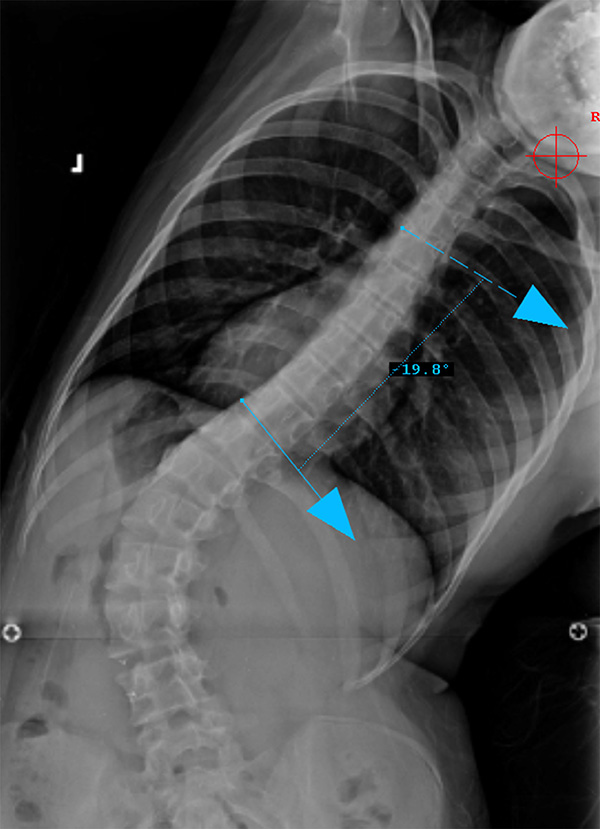

Sagittal Modifier N

T5-T12 in the 10-40o range

Preop PA View

Preop LAT View